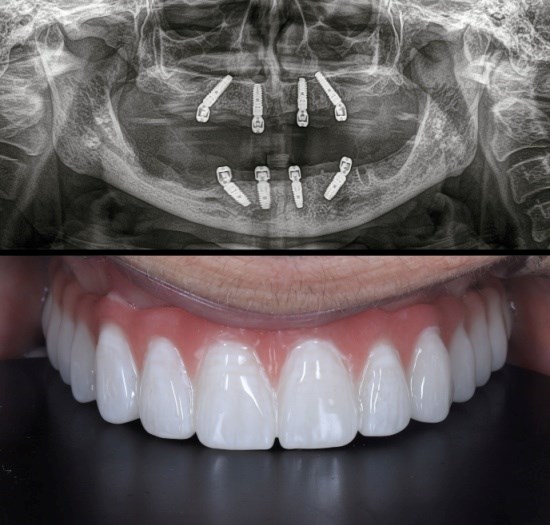

אחוזי הצלחה גבוהים לשתלי שיניים. צילום: שאטרסטוק

"דחייה אמיתית של שתל כמעט לא קיימת - הטיטניום הוא חומר שהגוף אוהב ולא מזהה אותו כגוף זר. מה כן יכול לגרום לכישלון? עישון כבד שמפריע לריפוי, חוסר היגיינה שגורם לדלקת סביב השתל, מחלות לא מאוזנות כמו סוכרת, או עומס יתר מוקדם מדי על השתל - כלומר, ללעוס עליו לפני שהוא נקלט כמו שצריך. בפועל, אחוזי ההצלחה מאוד גבוהים, מעל 95%. זה אחד הטיפולים הכי מוצלחים ברפואת השיניים".